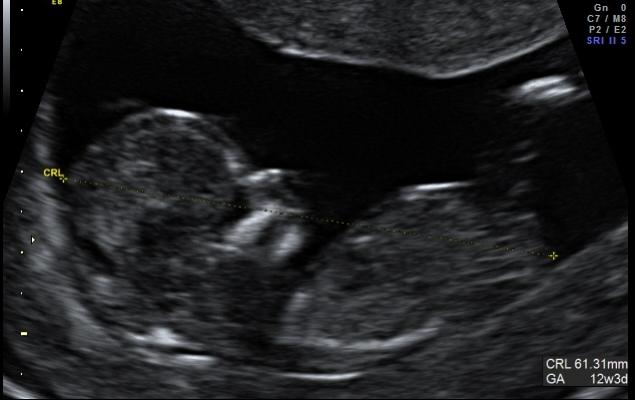

I have attached two profile shots from my 12w3d scan and although I have read a bit on nub theory I really cant tell if there is even a nub there or if its just part of the cord. Would anyone like to put their opinion forward :bigsmile:

Attachment 116Attachment 117